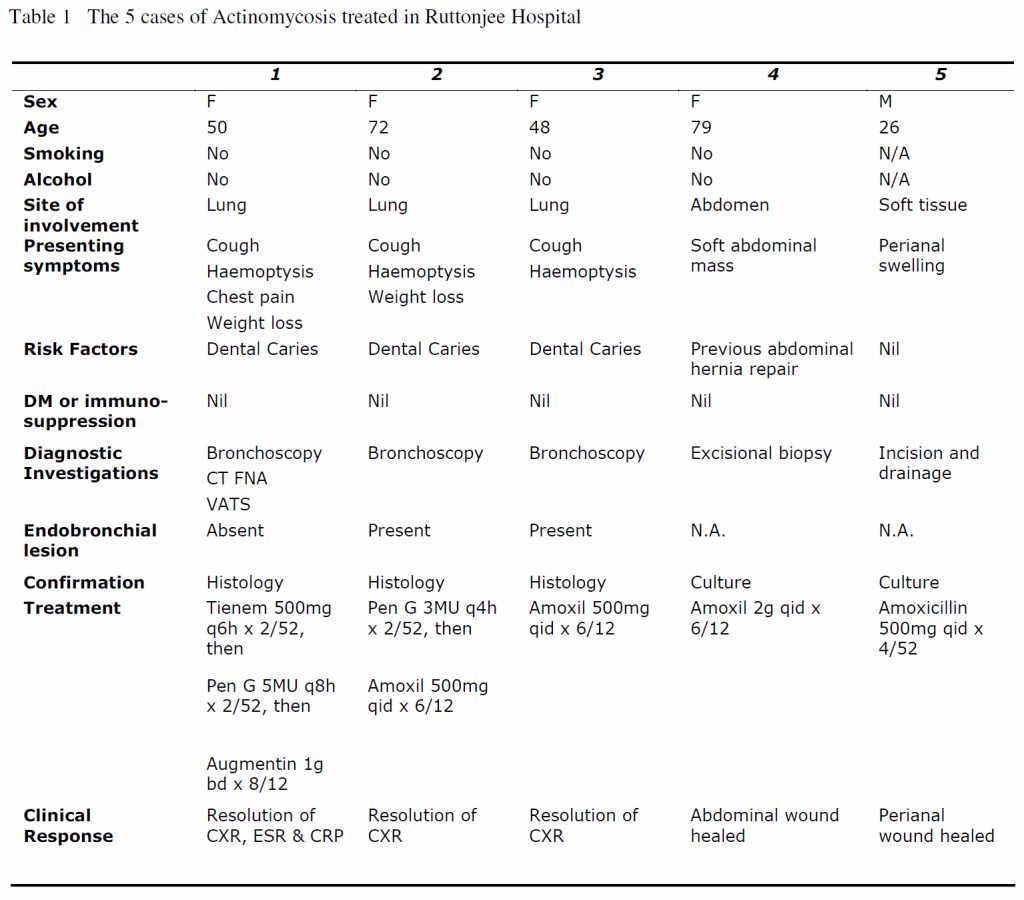

There were 10 cases of actinomycosis reported in Hong Kong East cluster over the past 10 years and 5 of those cases were treated in Ruttonjee Hospital (Table 1). Penicillin remains the drug of choice for Actinomycosis. IV antibiotics therapy for 2-6 weeks followed by 6-12 months of oral antibiotic therapy is usually recommended for thoracic actinomycosis.